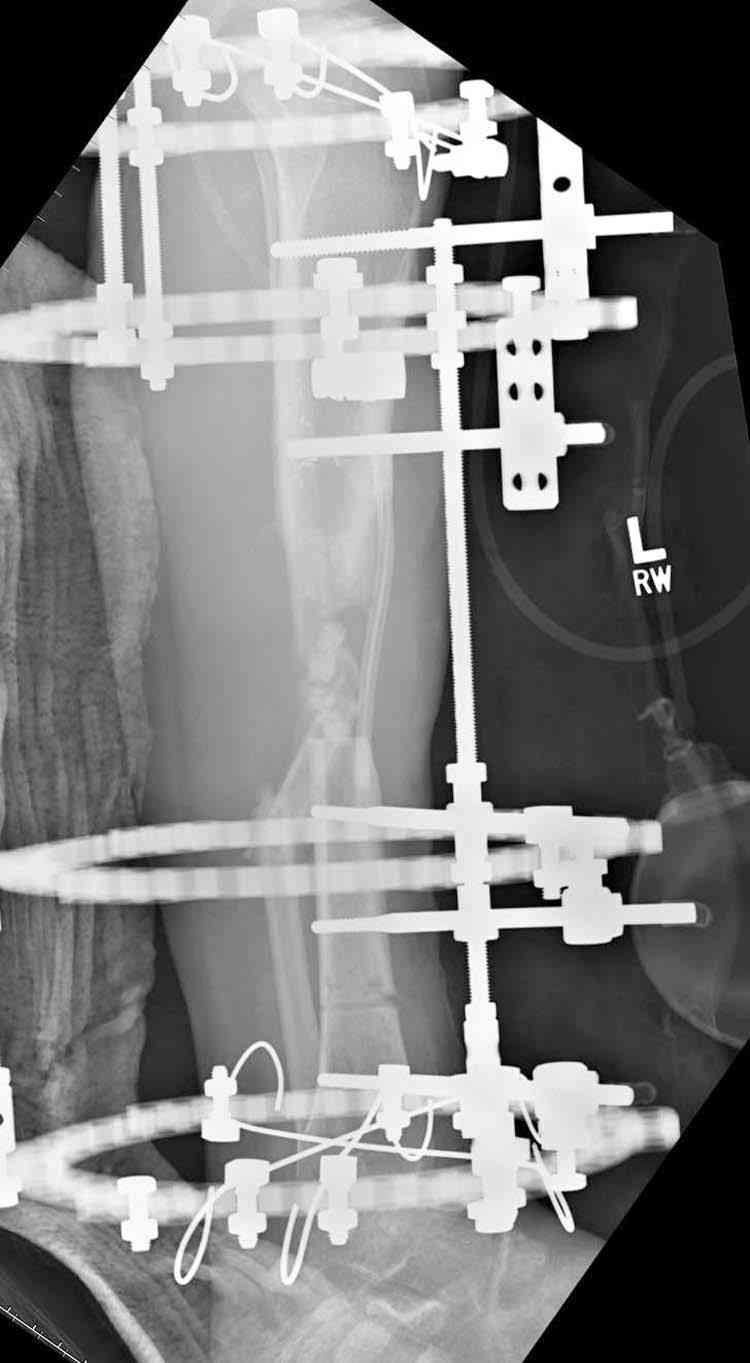

Re: case tibial defect

Согласен с тобой, короткий дистальный фрагмент, нет места ни для штифта, ни Т-образной пластины, да и шурупы мешают.

сделать поперечную остеотомию диафиза, полость заполнить antibiotic beads и начать удлинение.

Из аппаратов предпочтительно циркулярный, на дистальном фрагменте можно увеличить количество спиц.

Здесь случай, хотя не тот уровень, но принцип "удлинения после заполнения дефекта Antibiotic Beads" сохранен, можно немного увеличить количество бус.